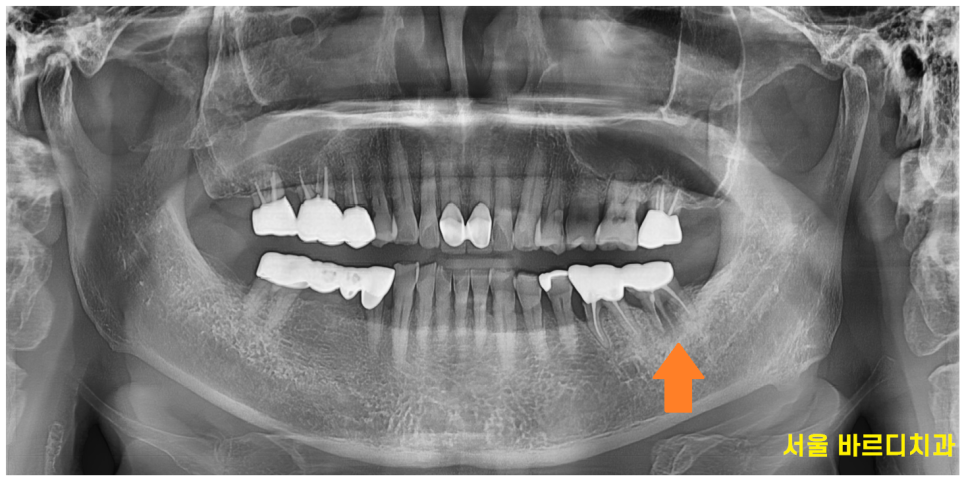

검진을 위하여 촬영해본 x ray

왼쪽 아래 치아가 문제가 있어보입니다.

치아 뿌리가 부러진 것처럼 보이는데요~